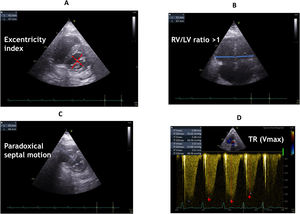

Using a basic approach, the cause of the shock towards PE when we observe the evidence of hyperechogenic images in the right cavities, in this context, has a high specificity of PE. Additionally, signs of the consequences of acutely increased pulmonary artery/right heart pressures can be observed including dilatation of right heart chambers and more precisely the evolution of an initial abnormal ratio of RV diameter or area to LV diameter or area (Fig. 4, Video 3).

Indices of right ventricle dilation and/or pulmonary hypertension: parasternal short-axis view at the mid-ventricular level illustrating measurements of left ventricular diameters for calculation of the eccentricity index (A), and assessment of septal motion (C), right and left ventricle basal diameter ratio in apical 4-chamber view (B), peak velocity of tricuspid regurgitation (TR Vmax) obtained in apical 4-chamber view with continuous wave Doppler through tricuspid valve (D).

Tricuspid regurgitation is frequent in patients with intermediate-to-high-risk pulmonary embolism. It allows the estimation of RV systolic pressure and thus of pulmonary arterial systolic pressure (PAsP) in the absence of pulmonary valve stenosis. PAsP can be estimated from the peak velocity of the tricuspid regurgitation (TR) jet (V) according to the simplified Bernoulli equation but may underestimate it when tricuspid regurgitation is very severe (Fig. 4D).